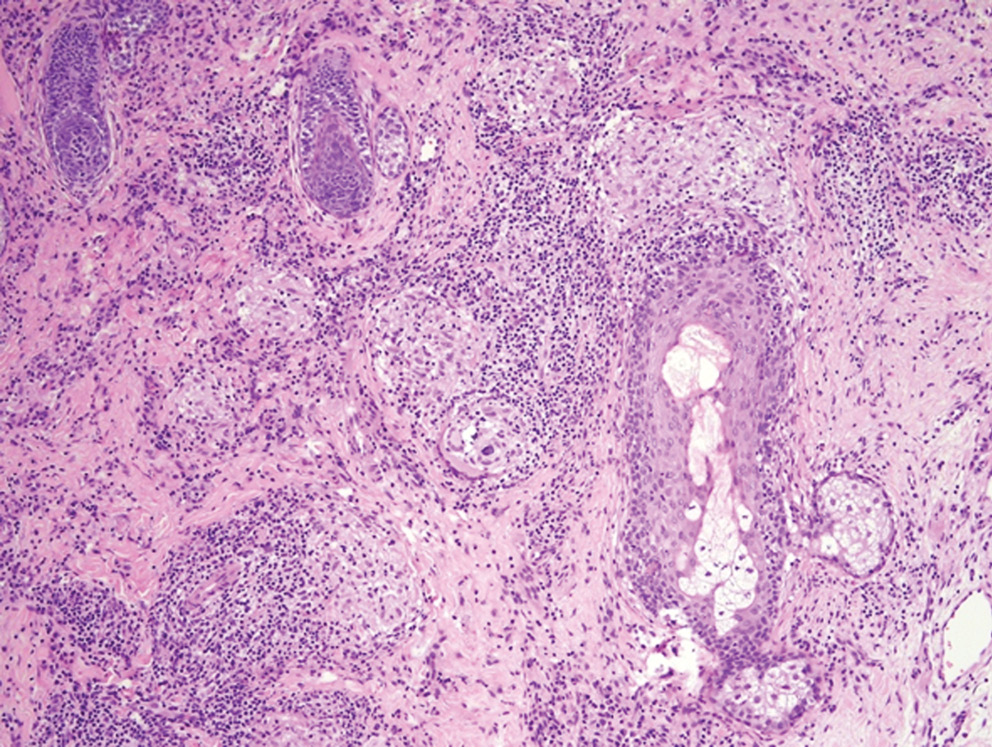

С целью уточнения диагноза проведена диагностическая биопсия кожи. При гистологическом исследовании в дерме на фоне отека были обнаружены многочисленные мелкие эпителиоидно-клеточные гранулемы саркоидного типа, без признаков казеозного некроза. К некоторым гранулемам прилегали очаговые лимфоцитарные инфильтраты (рис. 2, 3). При окраске PAS и по Циль–Нильсену микрорганизмов не выявлено.

Рис. 2. Гранулематозный инфильтрат в дерме на фоне отека

Fig.2. Granulomatous infiltrate in the dermis with edema

Рис. 3. Дермальные инфильтраты из многочисленных мелких гранулем саркоидного типа без признаков казеозного некроза. К некоторым гранулемам прилегают очаговые лимфоцитарные инфильтраты

Fig. 3. Dermal infiltrates consisting of numerous small sarcoid-type granulomas without signs of caseous necrosis. Some granulomas are adjacent to focal lymphocytic infiltrates